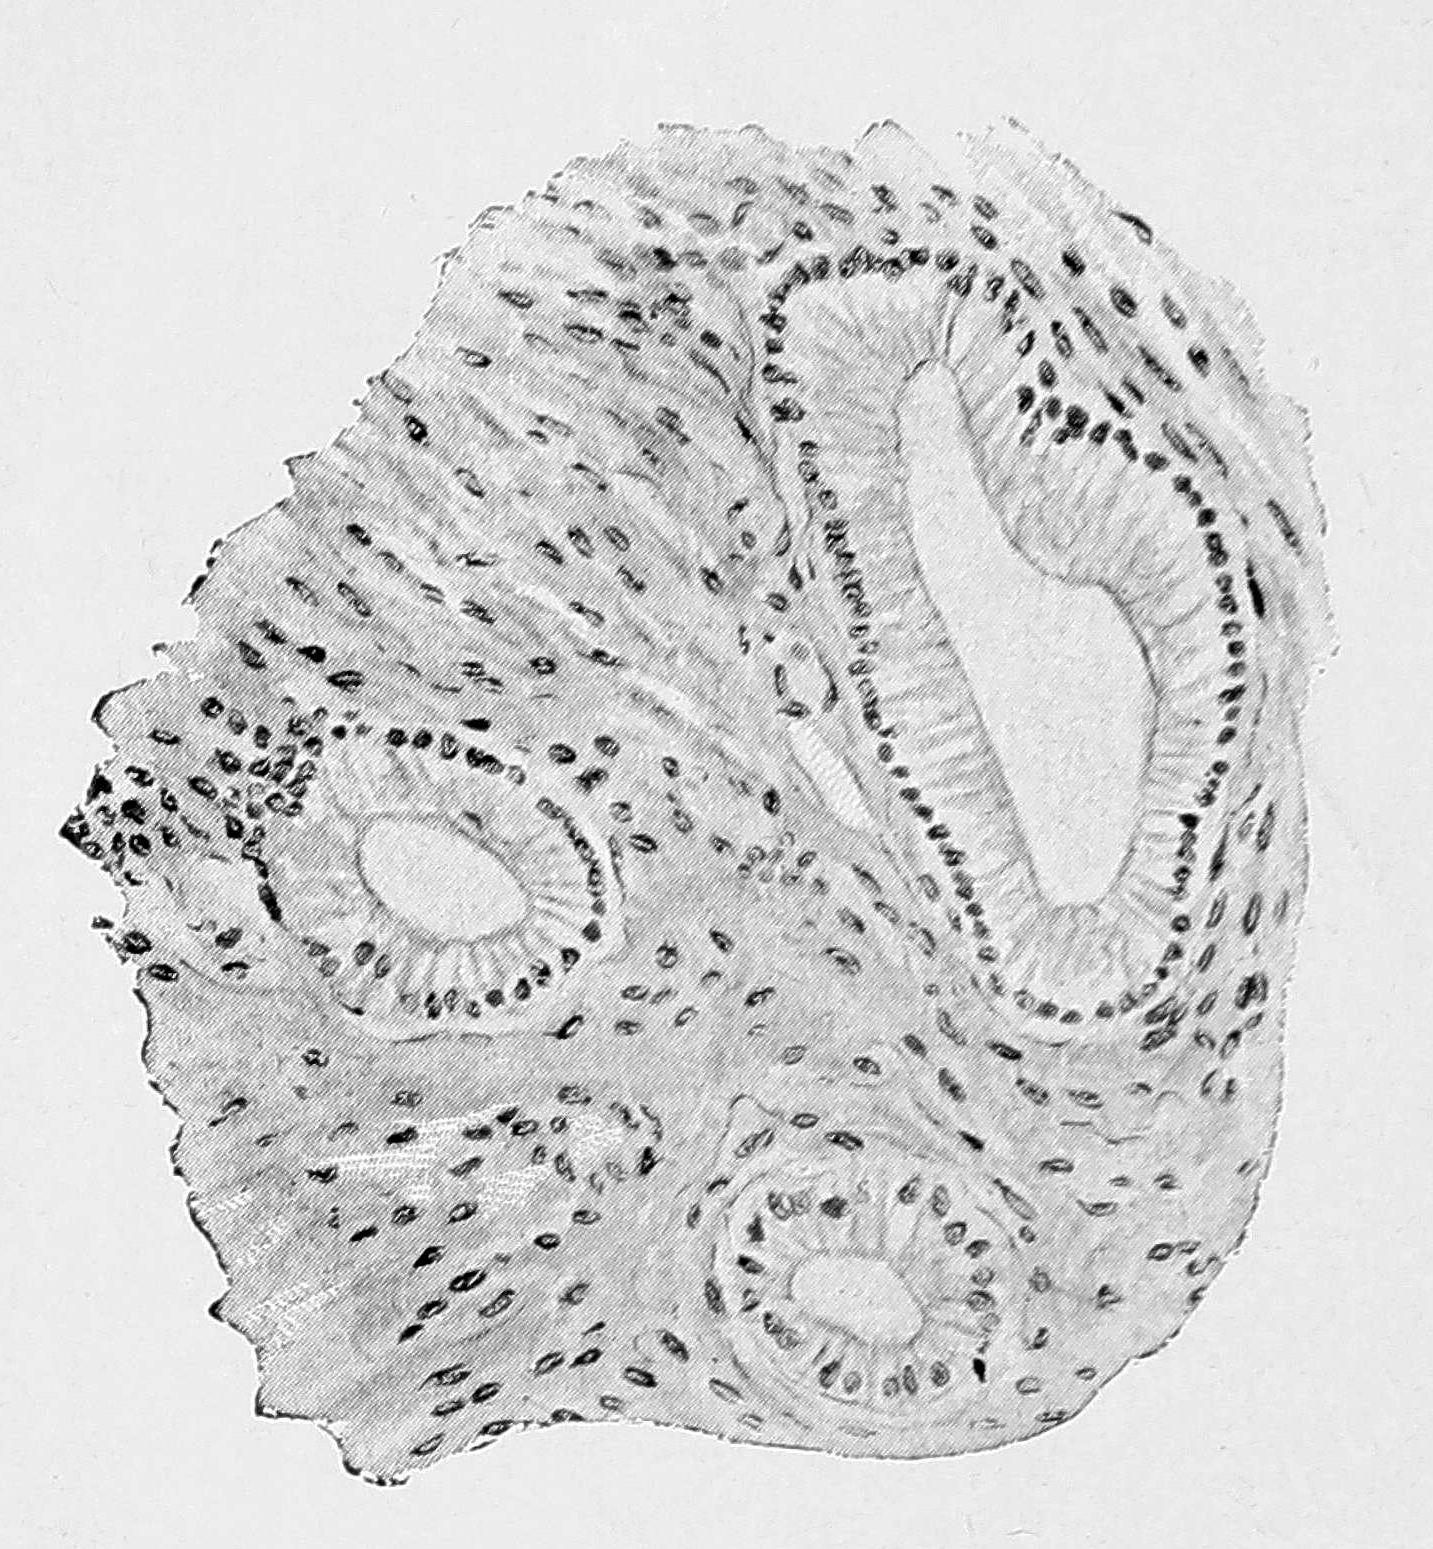

Слизистая оболочка тела матки явлений гиперплазии и гипертрофии не обнаруживала, местами представлялась даже атрофированной, но, в то же время, давала нерезко выраженное вростание желез в толщу миометрия, так что в нижней трети тела матки во внутренних слоях миометрия можно было встретить железистые включения двоякого типа — и типа желез эндометрия тела матки, и железы цервикального типа (см. рис. 1 и 2).

Рис. 1. Микрофотограмма среза матки с железистыми разростаниями типа желез цервикального канала. Zeiss. Ob. DD, Ос. III.

Рис. 2. Цервикальные железы в дне матки при сильном увеличении. Zeiss, Apoch. 16, Comp.-ocul. 12.